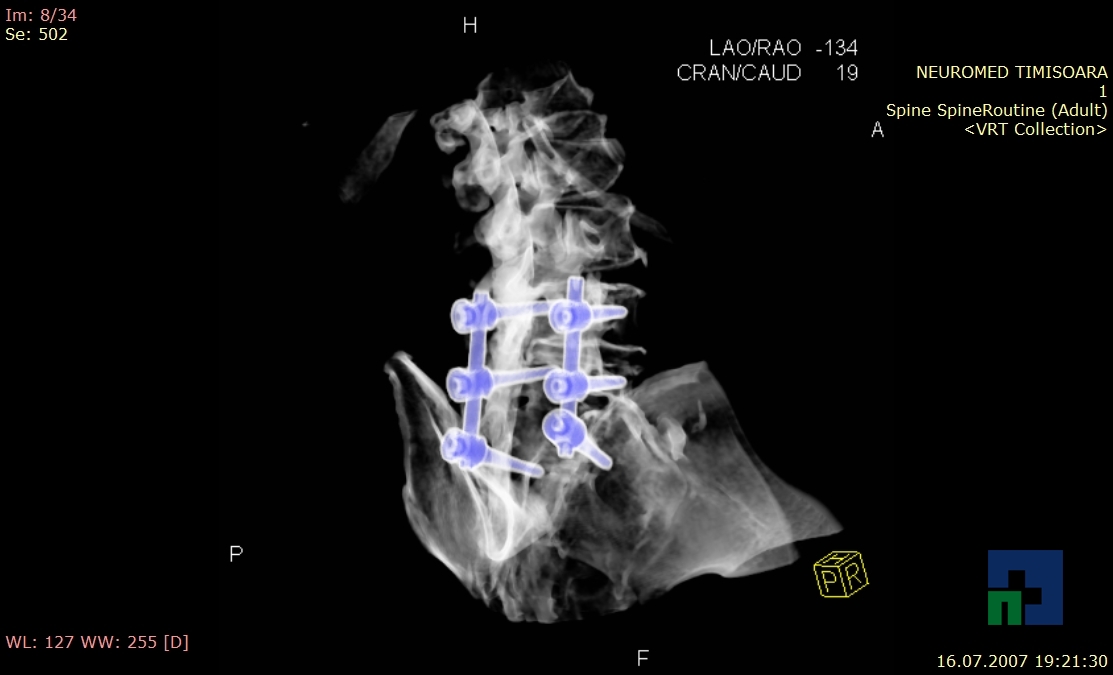

În cazul traumatismelor cranio-cerebrale:

- Diagnosticul fracturilor:

- Unice

- Multiple

- Cu înfundare

- Complexe cranio-sinusale

- Complexe cranio-etmoidale

- Complexe cranio-orbitare

- Complexe cranio-faciale